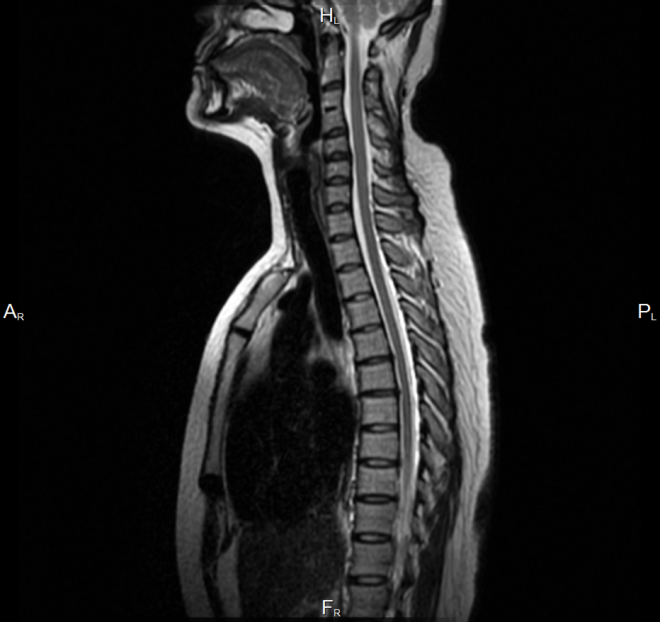

МРТ позвоночника - это томографическое комплексное обследование различных зон позвоночного столба. Магнитно-резонансный метод диагностики может с точностью определить даже мельчайшие повреждения в позвоночнике, чтобы начать своевременное и правильное лечение. Томографический аппарат с помощью мелкого шага сканирования, доходящего до 1 мм, позволяет врачам увидеть анатомически точные снимки любых структур - позвонков, спинного мозга, межпозвоночных дисков, нервных отростков, мышц и суставов. Важным преимуществом магнитной томографии позвоночника является возможность получения изображений в разных проекциях. Трехмерные томограммы дают возможность врачам рассмотреть всесторонне область сканирования и не ошибиться с диагнозом.

Многие неврологи считают, что магнитно-резонансная томография является наиболее оптимальным методом для исследования позвоночника ввиду того, что этот способ обследования безвреден, нет никакой лучевой нагрузки на организм, и его можно применять к разным категориям пациентов, например при беременности, для обследования детей любого возраста и раковых больных. С диагностической точки зрения магнитно-резонансное исследование дает специалистам высокоточные данные по состоянию костей, межпозвоночных дисков, сухожилий, хрящей, сосудов, мышц, нервных каналов, связок, спинного мозга. На снимках МРТ позвоночника врачи четко смогут увидеть признаки таких заболеваний и состояний, как: